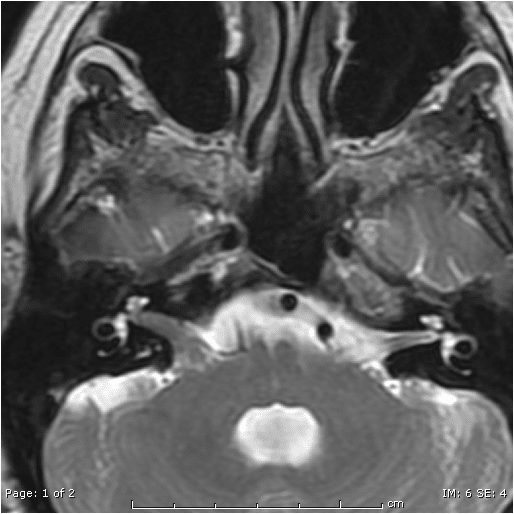

Acoustic Neuroma Types, Symptoms, Causes, Treatments, Surgery, MRI

Acoustic Neuroma Vestibular Schwannoma Diagnosis and treatment Per Does Acoustic Neuroma Cause Vertigo acoustic neuromas arise from schwann cells, which wrap around and support nerve fibers, hence the name vestibular schwannoma. the sensation that you're moving or spinning (vertigo) a large acoustic neuroma can also sometimes cause: This is a false sensation of movement, commonly spinning. Acoustic neuromas grow very slowly. acoustic neuromas can also cause dizziness and problems with. Does Acoustic Neuroma Cause Vertigo.